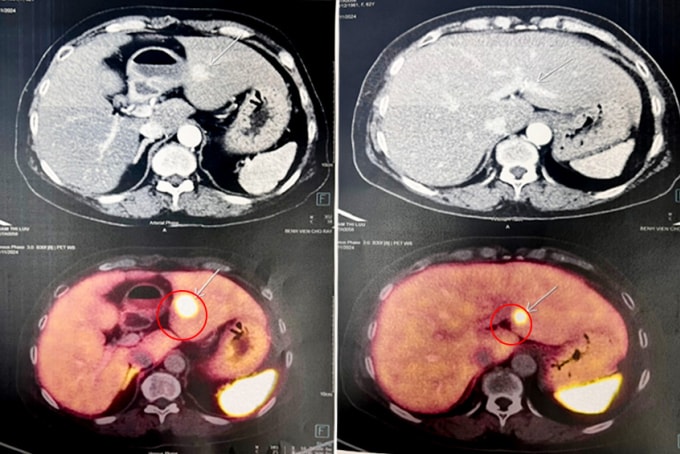

Chỉ số xét nghiệm đường huyết, huyết áp, chức năng gan thận của bà Long tại Bệnh viện Đa khoa Tâm Anh TP HCM đều trong giới hạn bình thường. Chụp CT phát hiện 6 khối u rải rác khắp cơ thể gồm hai khối u tuyến cận giáp kích thước 1,2 cm và 1,7 cm, một khối u ở ngực phải, một u ở gan và hai u ở tụy. Sinh thiết xác định u ở gan và tụy là u thần kinh nội tiết. Bà Long còn bị loãng xương ở vùng cột sống thắt lưng, cường cận giáp.

Ổn định sau phẫu thuật tuyến giáp, bà Long được điều trị các khối u gan và tụy còn lại. Khối u gan được đốt bằng sóng cao tần. Khối u ở thân tụy có kích thước dưới 2 cm, nằm ở vị trí không thuận lợi, không thể đốt sóng cao tần mà chỉ theo dõi và điều trị nội khoa.